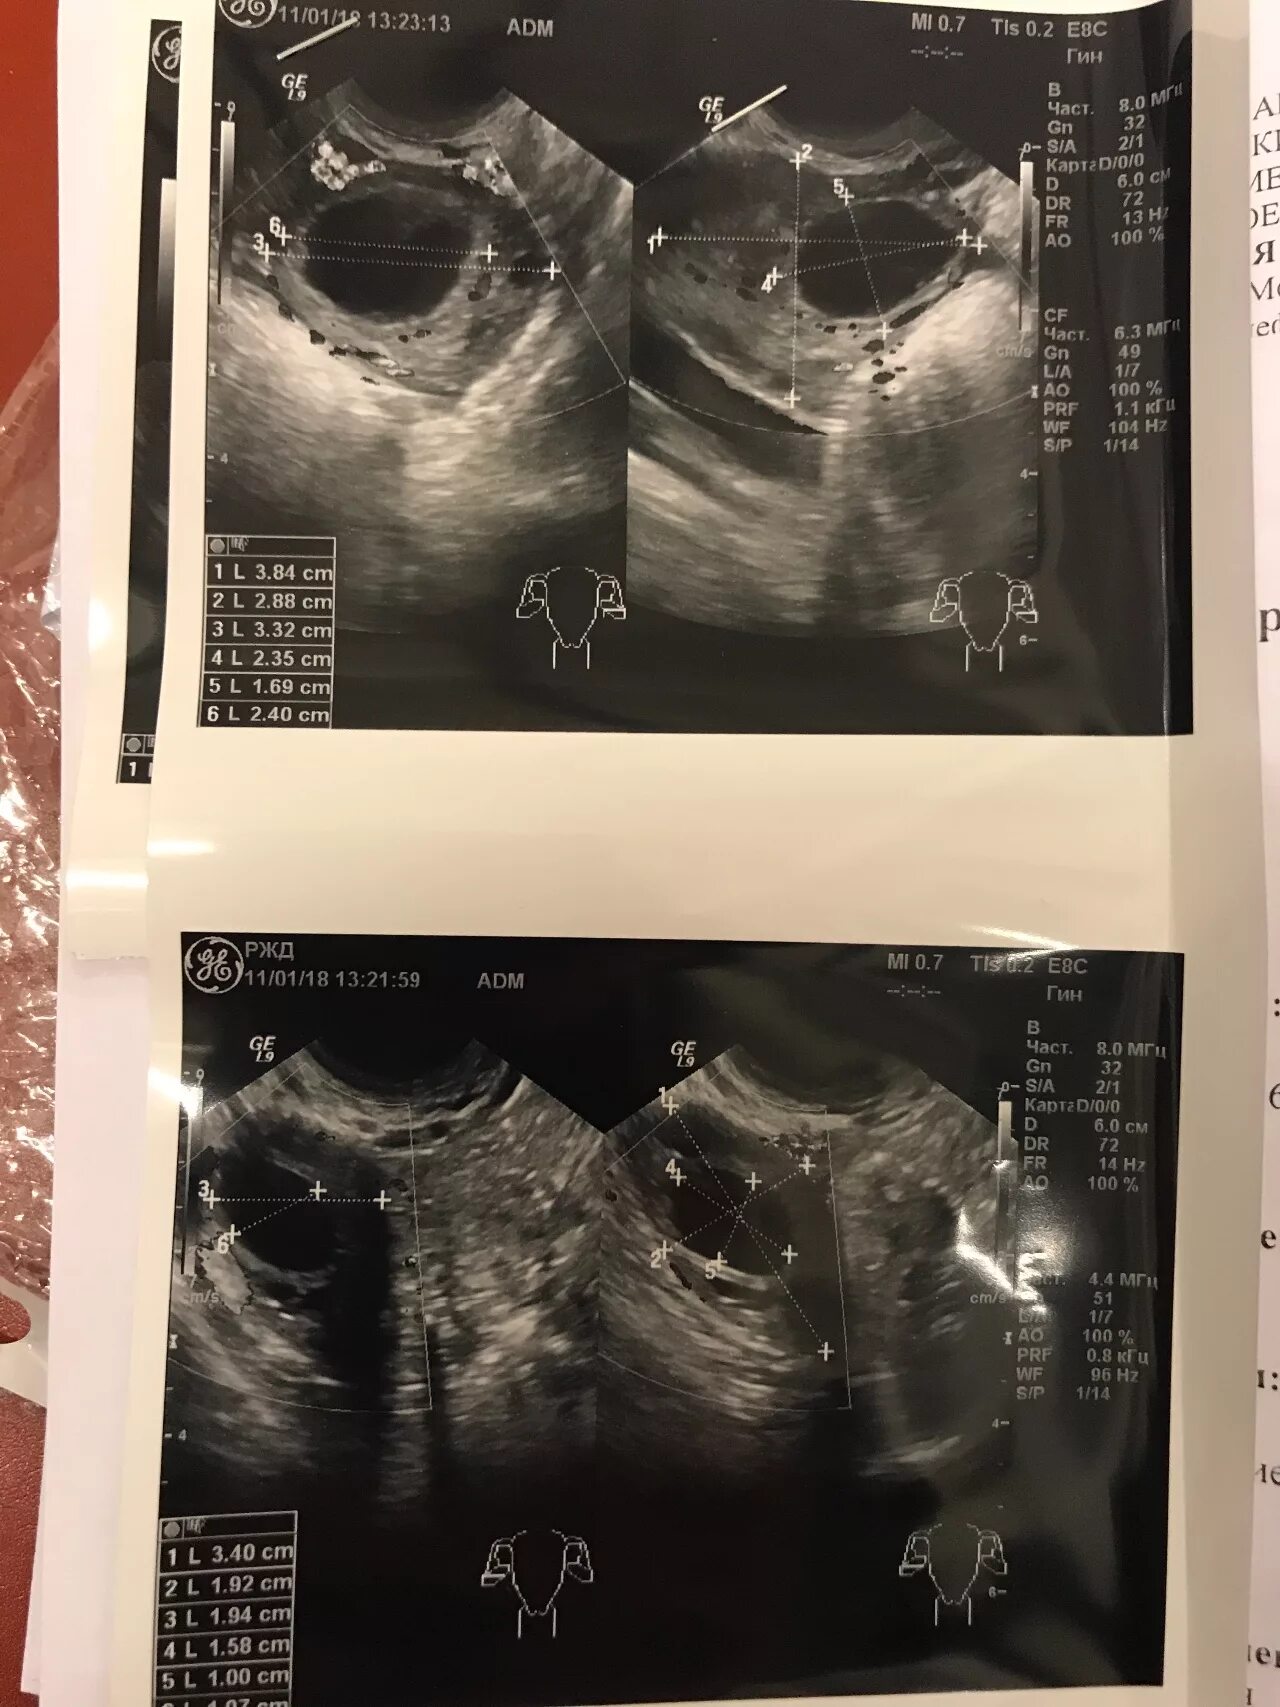

Фолликул 18 мм